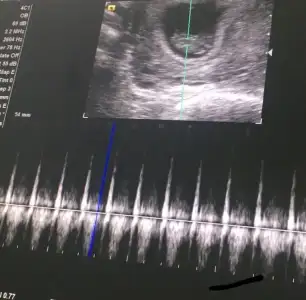

Kızlar minnoşun kalp atışlarını dinledim çok güzeldi :) sat ile uyumlu 24 mm olmuş 9+1 deyiz :KK54:

• 3DBF442B-9D15-44B0-AD5A-DA27001B9364.webp

3DBF442B-9D15-44B0-AD5A-DA27001B9364.webp

19,3 KB · Görüntüleme: 71